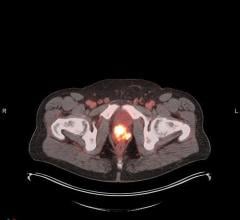

The "Guidance and Best Practices for Nuclear Cardiology Laboratories During the Coronavirus Disease 2019 (COVID-19) Pandemic: An Information Statement from ASNC and SNMMI," address principles for COVID-19 protection and offer specific recommendations for adapting nuclear cardiology practices at each step in a patient’s journey through the lab—for inpatients, outpatients and emergency department patients.

• An infographic detailing key steps for minimizing COVID-19 exposure in the nuclear cardiology lab.